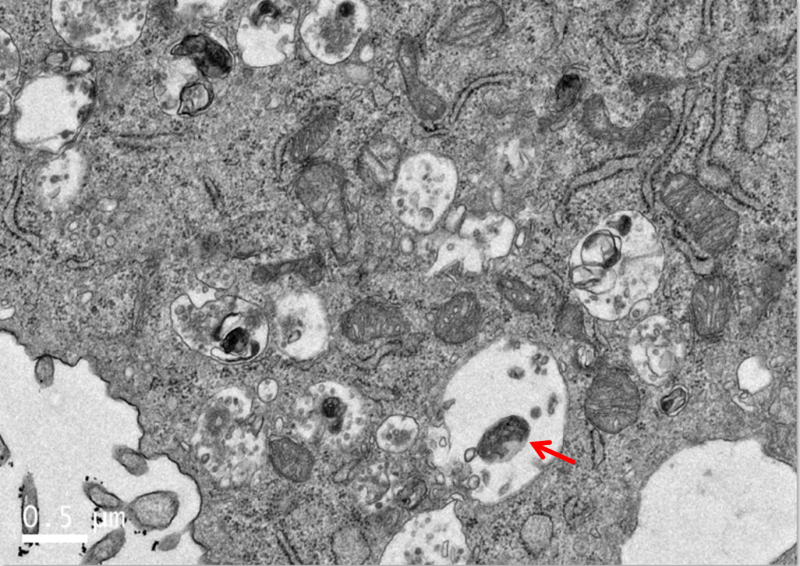

TEM 细胞图片观察请教 已有1人参与